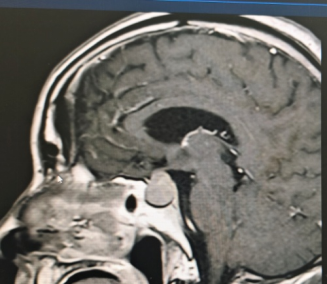

患者为69岁男性,因持续性头痛、视力下降伴双眼颞侧视野缺损前往阆中市人民医院神经外科就诊。经综合评估,结合内分泌检查及1.5T MRI动态增强扫描,确诊为垂体大腺瘤(2.0cm×1.7cm×1.7cm),肿瘤向上压迫视交叉,并伴有蝶窦气化不良。

针对该病例,垂体瘤多学科诊疗中心(MDT)多次组织讨论。鉴于传统开颅手术创伤大、恢复周期长,团队最终决定采用经鼻蝶内镜垂体瘤切除术。该微创技术通过鼻腔自然通道进入蝶鞍区切除肿瘤,具有创伤小、出血少、恢复快等优势。

手术过程中,团队在神经导航精准定位下,经鼻腔自然通道建立微创手术入路,完整切除肿瘤的同时最大限度保护正常组织结构,手术切口仅约2.0×1.5cm。术后患者恢复良好,无并发症发生,症状明显改善,目前已康复出院。